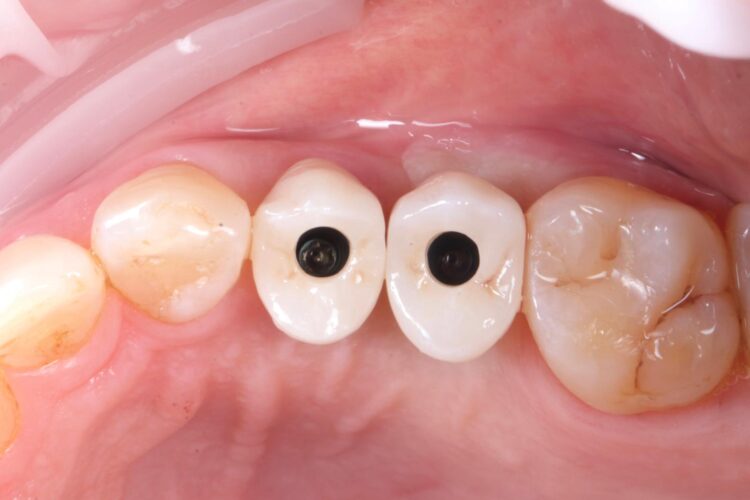

The implant in the UL5 was uncovered 3 months later to reveal healthy tissues. Three weeks later the final scan was taken (using trios intra-oral scanner) for the fabrication of the definitive crowns. On the day of crown fits both abutments were removed and the crowns seated. Due to the UL4 site having a custom healing abutment, which had been supporting our ideal emergence profile, it was much easier to engage this restoration and seat within the already moulded soft tissues.

With regards to the UL5 there was some blanching around the buccal aspect of the crown due to the use of a generic abutment, which does not offer any resemblance to the ideal emergence profile for the final restoration. Regardless good prosthetic positioning had been achieved to allow for screw-retained restorations in both implants. The final restorations were fitted as single unit layered zirconia crowns on titanium bases. The patient was delighted with the results.

Upon reflection of this case, a custom healing abutment may have delivered better soft tissue contouring than the generic abutment on the UL5. Healing may have taken longer, but it would have been easily tolerated by the patient and may have resulted in a better biological result with optimised aesthetics.